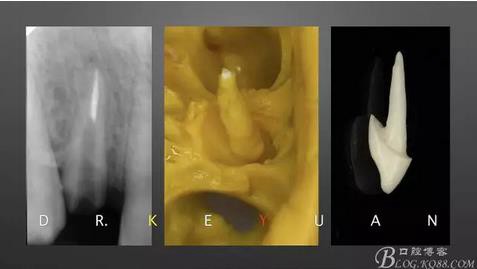

CASE 3—16歲少年外傷后一周來診,RCT后纖維樁及樹脂功能恢復(fù)

360截圖20170120135051661.jpg

一個(gè)牙髓壞死,一個(gè)活髓,首先一次性根管治療

360截圖20170120135100196.jpg

取研究模型,制作蠟型